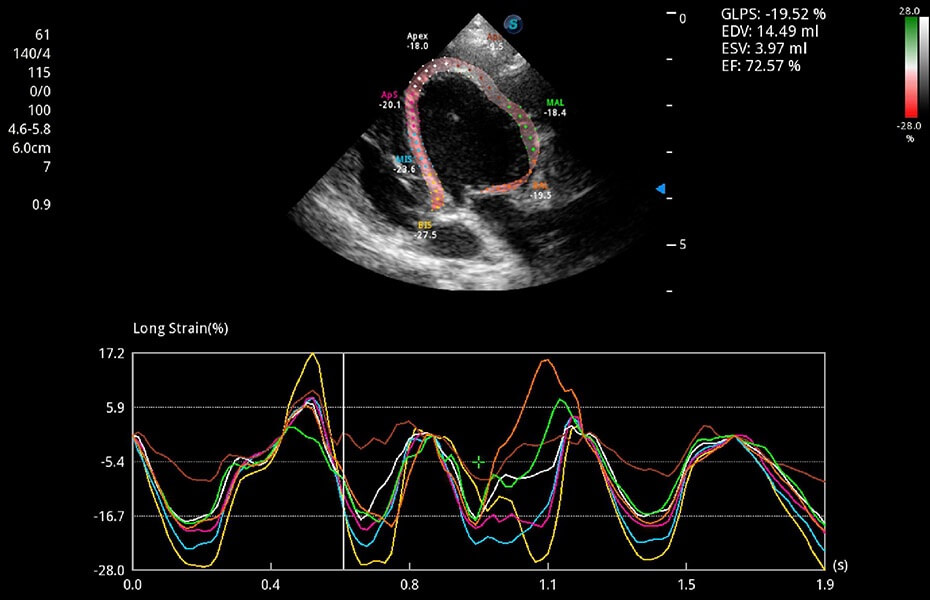

ProPet 60 作為一款高端臺(tái)式動(dòng)物超聲設(shè)備,為動(dòng)物醫(yī)生的日常診斷提供了一系列貼合動(dòng)物臨床需求、解決臨床實(shí)際問題的高級(jí)成像功能。憑借全系列高清探頭,滿足醫(yī)生對(duì)腹部、心臟、生殖、淺表、肌骨等成像的所有需求,切實(shí)幫助您提升檢查效率,提高診斷信心。